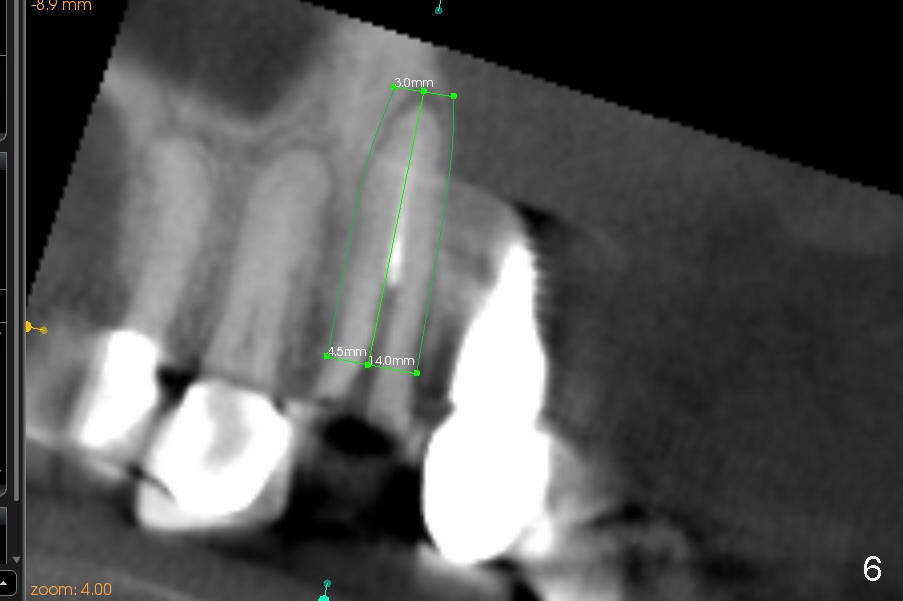

CBCT studies reveal that the implant perforates the buccal plate at the site of #7 and that there is still enough bone to support 3.0x17 mm one piece implant (Fig.2,3).  There is limited bone apical to the tooth #6.  The implant should be at least 17 mm for bone level and 14 mm for tissue level (Fig.4) or preferably 20 mm with sinus lift (Fig.5).  The diameter will be 4.5 mm (Fig.6) or 5 mm (Fig.4.5).